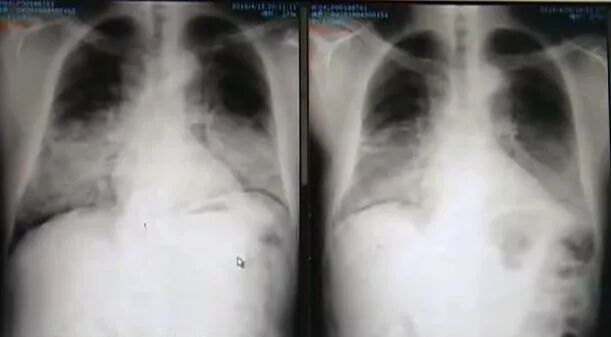

便在当地医院做了胸部 CT 检查

却发现双肺已经变白了

医生诊断为肺泡蛋白沉积症